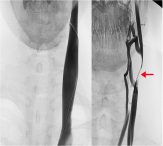

At 1 year follow up the EDSS was 3 again and the patient reported recurrent fatigue that she had been experiencing for several months. Further investigation revealed a CCSVI related left IJV tandem obstruction. At mid cervical level B-mode color Doppler demonstrated an IJV obstruction mirrored by an MRV imaging. In both cases a pencil tip pencil sign was demonstrated (Figure 2). The color Doppler assessment highlighted a left IJV dynamic flow obstacle caused by an extrinsic compression (Figure 2), that could be relieved by yawning.

Considering a further PTA pointless, an open surgical access was placed. The macroscopic evidence of the extrinsic stricture, caused by a fibrotic and short OM intermediate tendon on the IJV, lead to the surgical transection of the two muscular bellies. In addition, endophlebectomy of the terminal IJV permitted the removal of a fibrotic septum. The procedure was completed by patch angioplasty by using an autologous great saphenous vein. The patient tolerated the procedure well and neither major nor minor complications were reported.